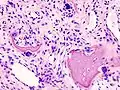

Histopathology of osteoarthrosis of a knee joint in an elderly female